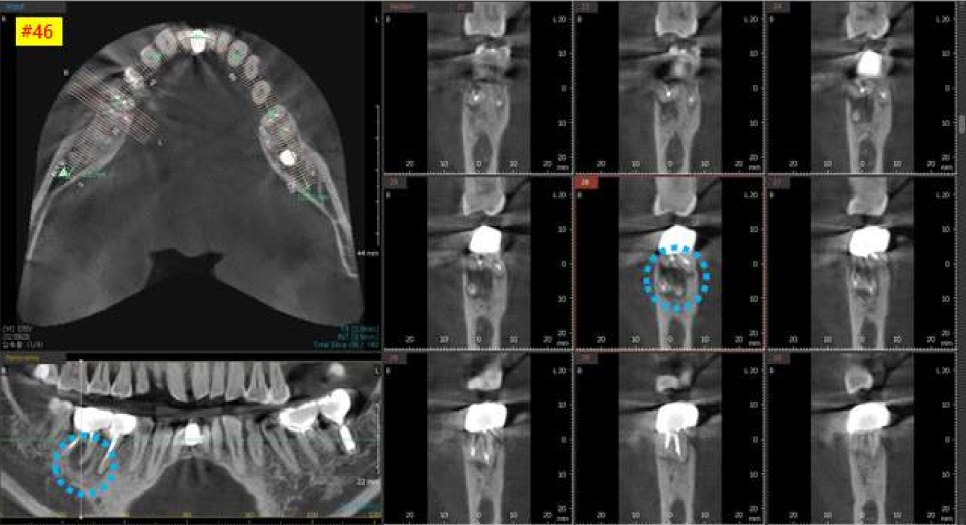

다음 오른쪽 아래 어금니의 3차원 CT 사진입니다.

보시면 까맣게 뼈가 녹아 있는 상태를 볼 수 있습니다.

치아 뿌리를 잡아주는 치조골이라는 뼈가

계속 염증으로 인하여 녹고 있는 상태입니다.

염증을 깨끗하게 제거하고

뼈이식을 같이 하기로 결정했습니다.

역시, 인접치 관계를 고려해서,

가장 이상적이고 안전한 위치를 찾아

적정한 두께와 길이의 임플란트를 선택했습니다.

다음 날, 오른쪽 아래 큰어금니 수술을 진행하였습니다.

아래 어금니 같은 경우에는

신경이 손상되지 않도록 수술하는 것이 가장 중요합니다.

어금니 뿌리 아래부분에 ‘하치조신경’이라는 신경이 지나가는데

손상되면 안면마비가 올 수 있기 때문에 항상 조심해야 합니다.

3차원 CT사진에서 빨간색으로 표시해놓은 신경관을

피할 수 있도록 CT를 분석하고

이에 맞는 직경과 길이의 임플란트를 선택하여

수술을 시작하였습니다.